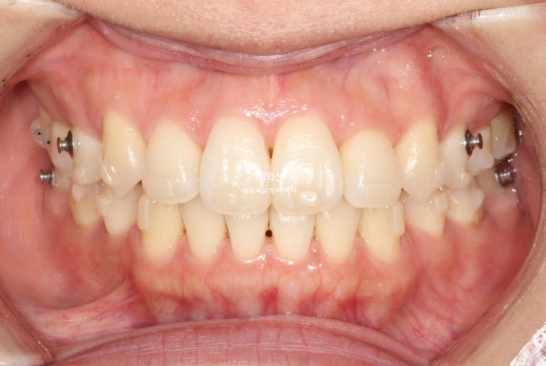

25.07

중심선은 일치하고

어금니 교합은 1급이고 물샐틈 없습니다.

23.01~25.07

유지장치까지 들어간 모습입니다.